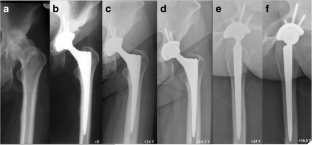

Fig. 1

Fig. 2

Fig. 3

Fig. 4

Fig. 5